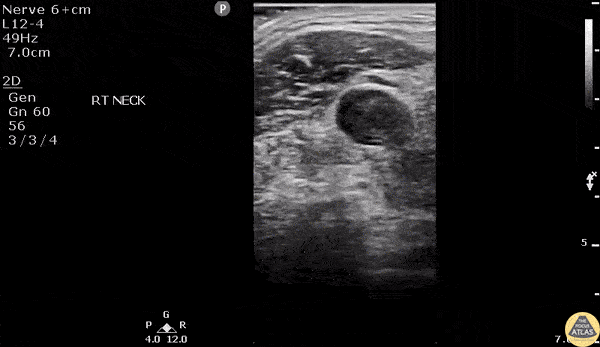

Vascular - Lemierre Syndrome

A young male presented to the ED with high fever and right lateral neck pain with swelling and associated chest pain. He has a recent history of a sore throat. Transverse view of the neck reveals IJ thrombus with enlarged surround lymph nodes. Chest CT revealed a septic pulmonary emboli. Image courtesy of Robert Jones DO, FACEP @RJonesSonoEM Director, Emergency Ultrasound; MetroHealth Medical Center; Professor, Case Western Reserve Medical School, Cleveland, OH View his original post here